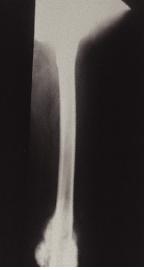

유잉 육종은 장관골의 한 가운데에 마치 벌레가 파먹은 모양의 골파괴 양상과 골형성이 혼합되어 있는 모습을 보입니다. 골막은 특징적으로 비후되어 양파껍질 모양이 관찰될 수 있습니다.

![]() [좌측 상완골 유잉육종] |

![]() [유잉육종] |